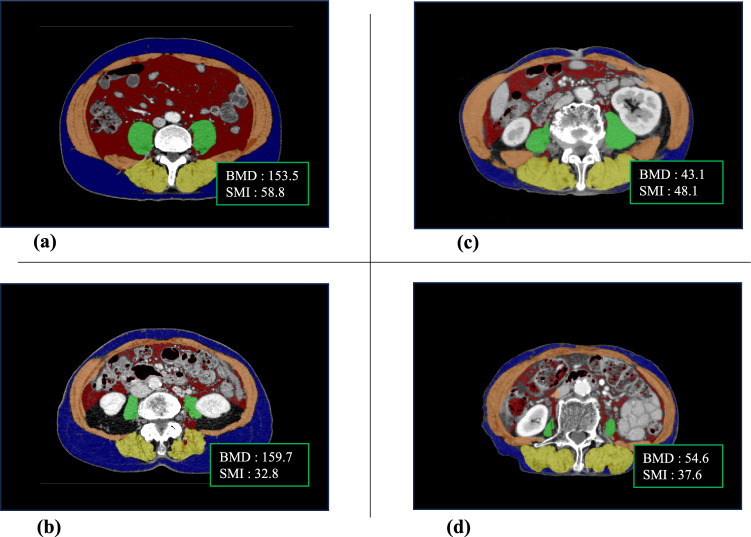

Methods: We analyzed the data of patients diagnosed with early gastric cancer and not eligible for endoscopic treatments, who underwent either distal gastrectomy or sentinel node navigation surgery at our hospital between 2010 and 2020. Skeletal muscle index and bone mineral density were measured preoperatively and 1, 3, and 5 years, postoperatively; rates of changes in these measures were assessed.

Results: Among the 63 patients included, 42 (67%) underwent conventional surgery, and 21 (33%) underwent function-preserving gastrectomy using the sentinel node technique. No significant difference in postoperative survival rates was observed between the two groups (P = 0.97). The rate of change in the skeletal muscle index and bone mineral density decreased in both groups from 1 to 3 years postoperatively. At 5 years postoperatively, the sentinel node navigation surgery group showed an increase in skeletal muscle index and bone mineral density change rates, the difference observed between the two groups was significant (P < 0.05).